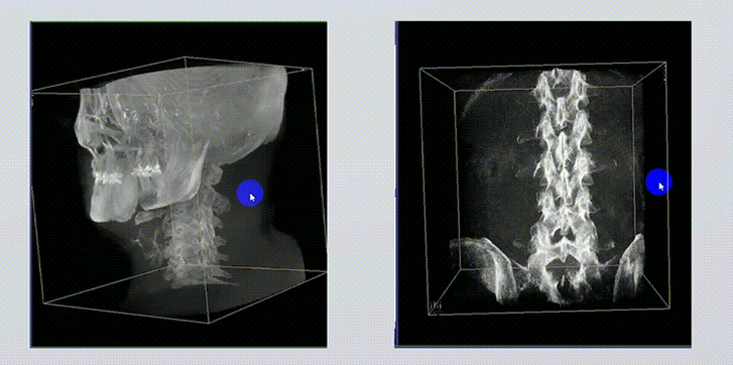

1、術(shù)中實(shí)時三維成像

術(shù)中三維成像和橫斷面圖像提供多角度的手術(shù)診斷信息,輔助醫(yī)生進(jìn)行術(shù)中評估判斷,諸如骨折復(fù)位情況和內(nèi)植入螺釘?shù)某叽绾臀恢茫o助手術(shù)更好地完成。

2、三維成像視野大

提供更大的術(shù)中三維成像視野,采集更多圖像信息,可一次拍全全段頸椎、全段腰椎、七節(jié)胸椎、雙側(cè)骶髂關(guān)節(jié)、股骨頭及單側(cè)盆骨。